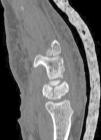

Figure 6.

Postoperative CT imaging where correct fracture reduction is observed together with the osteosynthesis screw positioning.